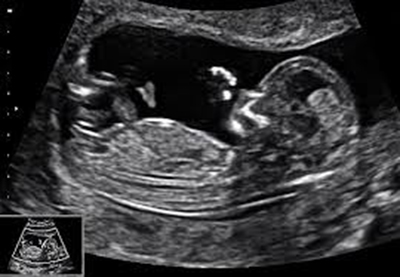

1st trimester ultrasound

First-trimester ultrasound must be performed between 11 and 14 weeks' amenorrhea (SA).

Outside these dates, certain parameters can no longer be assessed correctly, such as nuchal translucency or chorionicity in a multiple pregnancy.

It can be used to determine :

• Gestational age and pregnancy dating (date of onset of pregnancy and gestational age) by measuring the craniocaudal length of the embryo

• Pregnancy progression

• Determining the number of embryos and the type of multiple pregnancy (chorionicity and zygocity)

• Measurement of fetal neck thickness (nuchal translucency is correlated with the risk of fetal chromosomal abnormalities, particularly trisomy 21).

• Screening for certain fetal malformations: checking for the presence of the cephalic pole, four limbs, the integrity of the abdominal wall, the presence of a stomach and bladder.